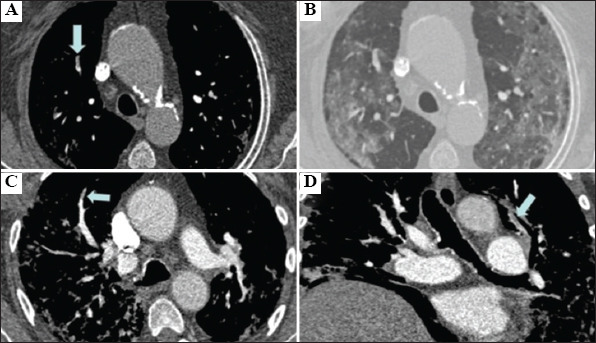

Abstract Image